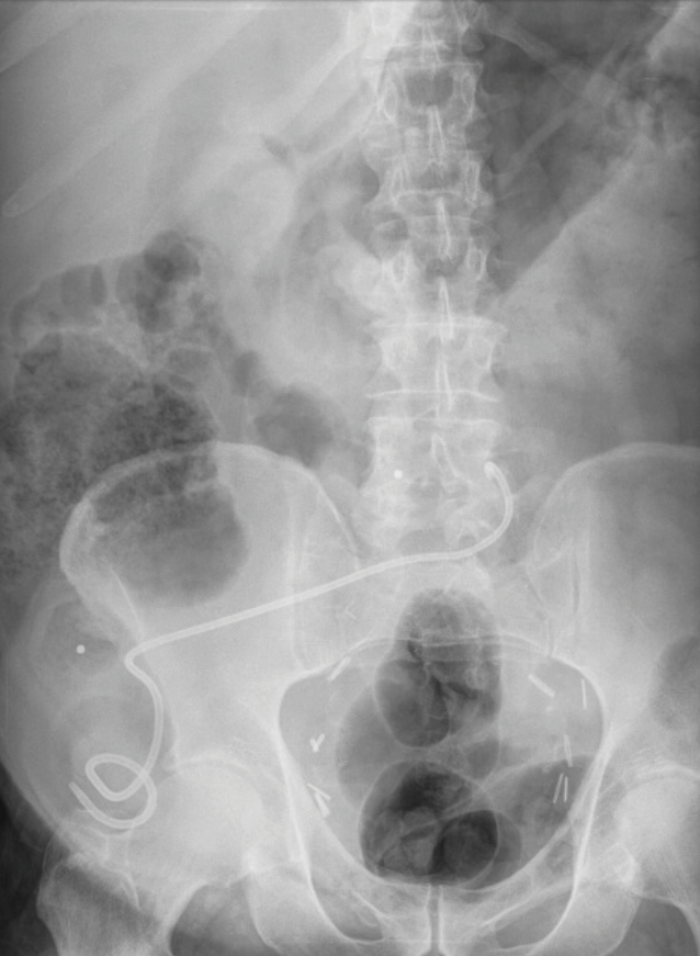

A nephrostogram at one week demonstrated good flow into the conduit and the nephrostomy was removed under fluoroscopic control. The patient presented five days later with the stent visible at the conduit opening (Figure 3). It was re-sited by the interventional radiologist by passing a guide wire through the stent and re-positioning it under fluoroscopy but displaced again a few days later. A subsequent CT confirmed the patient was stone free and the stent was above the level of the uretero-ileal anastomotic stricture. The stent was left in place as the uretero-ileal stricture was the likely cause of the stone forming. A further stent change was planned for three months’ time.

Figure 3: Plain radiograph demonstrating stent migration.